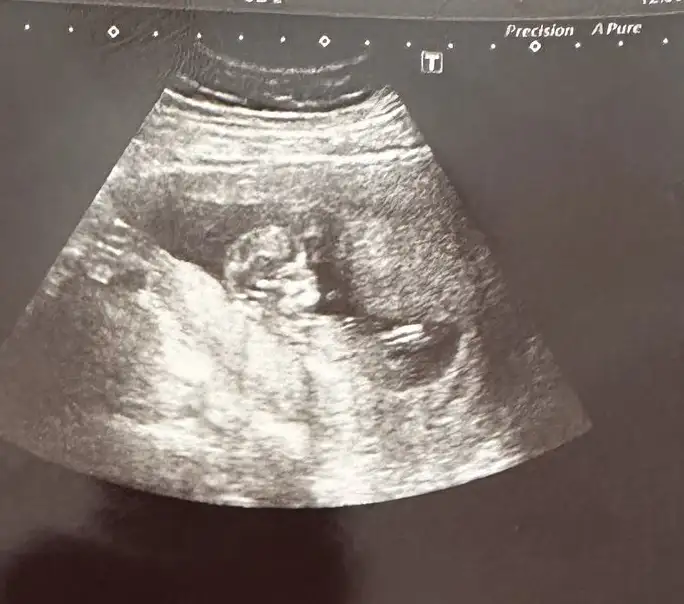

Bana da yorum yapabilir misiniz kızlar 7. Haftadan abdominal goruntu

Abdominal görüntüyse eğer kız olabilir ☺️🌸 ama sanki sizin ultrason görüntünüz ters gibi . Normalde dar olan kısım yukarda geniş olan kısım aşağıda olur. Bilemedim bu bebişe karar vermek zor çünkü görüntü tam tersiyse eğer erkek de olabilir ☺️ sağlıkla gelsin. Daha net bir görüntü olursa paylaşın ☺️